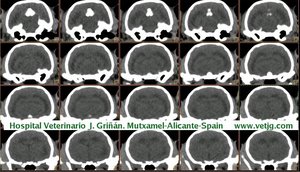

imágenes de TC en el gato | |||||||||||

Mismo paciente: Correspondencias entre el corte sagital y el volumen, ambos reconstruidos a partir de imágenes TC (transversales) |

Tomografía computarizada helicoidal |